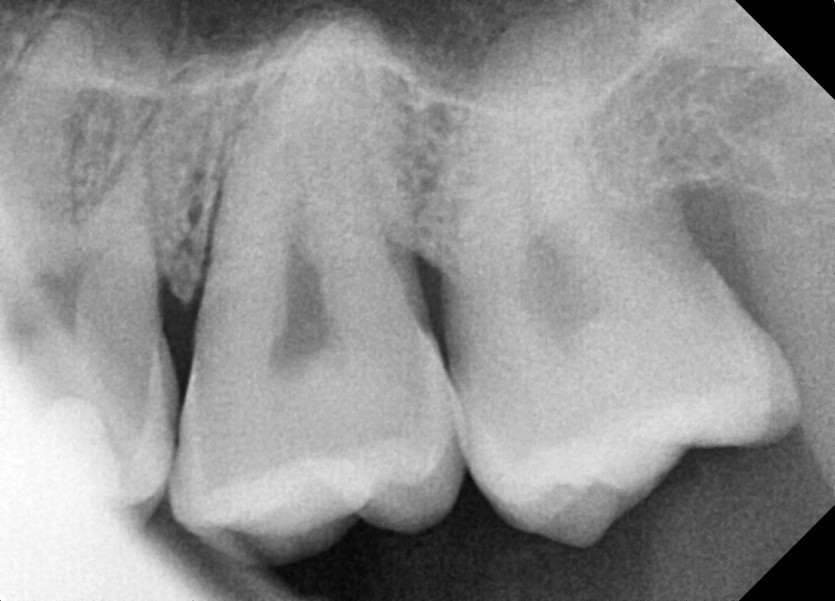

#18,28,38,48 사랑니 발치

구강 외과 전문의가 당일 발치했습니다.